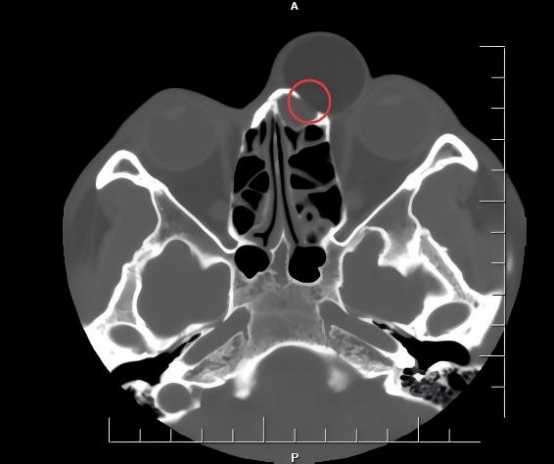

李先生自年幼时起,鼻根部就有一个小肿物,随着岁月流逝,至今已经29岁,这个原本不起眼的“小疙瘩”竟缓慢却持续地增大,如今已如鸽子蛋般大小。它不仅严重影响了李先生的面容,给他带来了巨大的心理压力,更压迫视野,导致日常生活极为不便。近几年来,肿物仍有增大趋势,随时可能进一步压迫眼球,引发更严重的并发症。经检查发现,由于肿物的长期压迫,其下方的鼻骨已被吸收殆尽,肿物甚至与鼻腔相通,病情复杂且棘手。

面对这一挑战,来自附属瑞金医院的援滇专家徐赫医生没有选择常规的鼻面部大切口,而是制定了周详且极具创意的手术方案。